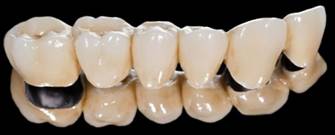

オールセラミッククラウン

「オールセラミッククラウン」は、土台はセラミックの一種であるジルコニアでつくり、その上にポーセレンを焼きつけます。

何年たっても歯ぐきが黒ずむことはありません。

ただし、これにも欠点がありポーセレンを焼きつけているので、使っているうちに欠けることがあります。

セラミッククラウンにはいくつか種類がありますが、もっとも一般的なのは「メタルボンド」といって、 金合金などの金属にポーセレン(陶材)を焼きつけたものです。

見た目はほかの歯と区別がつかないほど自然ですが、欠点もあります。 歯ぐきが下がってくると、金属とポーセレンの継ぎ目が見えたり、歯ぐきのきわが黒ずんだりします。